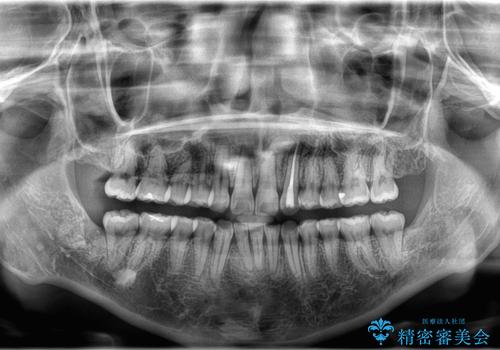

- 「歯の捻じれとがたつき」を主訴に来院された患者様です。

軽度な捻転と叢生だったため、インビザラインのモデレートで治療を行いわずか半年で治療を終える事が出来ました!

- 税込583,000円費用は治療当時の料金となります